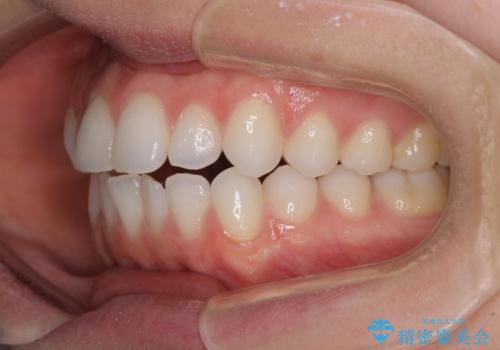

上下前歯が接触しない オープンバイトをインビザラインで改善

- 前歯の上下スペースによる食べにくさを気にして来院された患者様です。

インビザラインにより上下の前歯の隙間を閉じていくこととしました。

上下の奥歯を圧下させるようにすることで、前歯を接触させるように計画しました。

上下の隙間に舌が入り込むことがオープンバイトの原因であったため、舌の筋肉のトレーニングも並行して行い、後戻りの抑制を図りました。